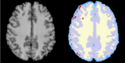

| − | * [[Image: | + | * [[Image:EMS LesionsExp BeforeAfter.png|125px]] '''Task 11: [[EMSegmenter-Tasks:LesionExp|White matter lesion segmentation''' ]] |

Task 11: White matter lesion segmentation